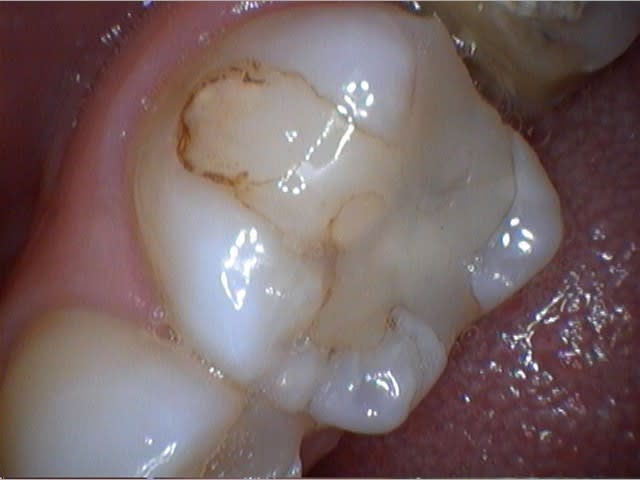

J'ai reçu la Camera intrabuccale 1/4 Sony CCD MD960u ce matin. Pas encore eu trop le temps de me pencher sur les réglage, mais voici ce que ça donne une fois installée et branchée...

Je trouve cela pas mal du tout pour une camera à 200€! :-)

Beaucoup mieux que la MD740, non?

Quelques photos prises ce matin au cours d'une longue séance de soins. Je posterais un test complet de la caméra bientôt pour ceux que ça intéresse...